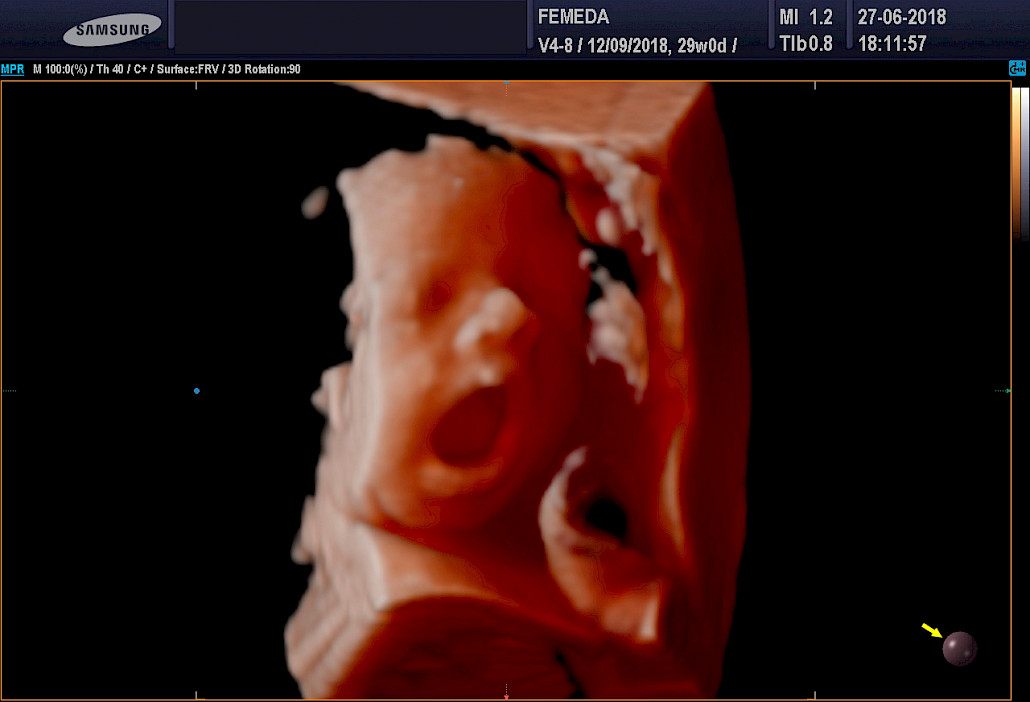

Ehdottomasti molemmat! 3D-tekniikalla tuotetaan staattista neulanterävää kolmiulotteista kuvaa. Se soveltuu sikiön kuvaamiseen, kun halutaan mahdollisimman tarkkaa ja korkealaatuista kuvaa. 4D-tekniikka on tarkoitettu erityisesti sikiön liikkuvaan ja kolmiulotteiseen kuvaamiseen.

3D ja 4D-tekniikat soveltuvat erityisen hyvin sikiön kasvojen anatomian tutkimiseen. Tutkimuksessa poissuljetaan mahdollinen huulihalkio ja kasvojen profiilissa esiintyvät muut poikkeamat, kuten liian pieni leuka. Samalla selvitetään korvien anatomia ja niiden sijainti. Tekniikan avulla selvitetään raajojen asennot, sekä sormien ja varpaiden lukumäärä ja niiden liikkuvuus. Lisäksi tutkitaan koko selkärangan rakenne ja suljetaan pois poikkeamat, kuten puuttuvat lapa- tai olkaluut.

4D-tutkimukset voidaan tehdään koska tahansa raskauden aikana. Sikiön rakenne voidaan selvittää kuitenkin parhaiten raskausviikoilla 19-30. Sikiön kasvonpiirteet näkyvät parhaiten raskausviikoilla 22-28. Niukka lapsiveden määrä, epäedullinen sikiön asento, äidin ylipaino tai paksut vatsanpeitteet saattavat vaikuttaa 4D-kuvien laatuun, mutta ne harvoin estävät tyydyttävän arvion saamista sikiön anatomiasta.

Sikiöstä otetut kolmiulotteiset kuvat ovat erittäin tarkkoja ja havainnollistavia – suorastaan kauniita. Kuvauksiin voi tulla millä tahansa raskausviikolla. Tutkimusta ei tarvitse pelätä ja tulevan lapsen isä ja sisarukset ovat myös lämpimästi tervetulleita. Tilanne on usein ikimuistoinen ja ainutkertainen kokemus koko perheelle.